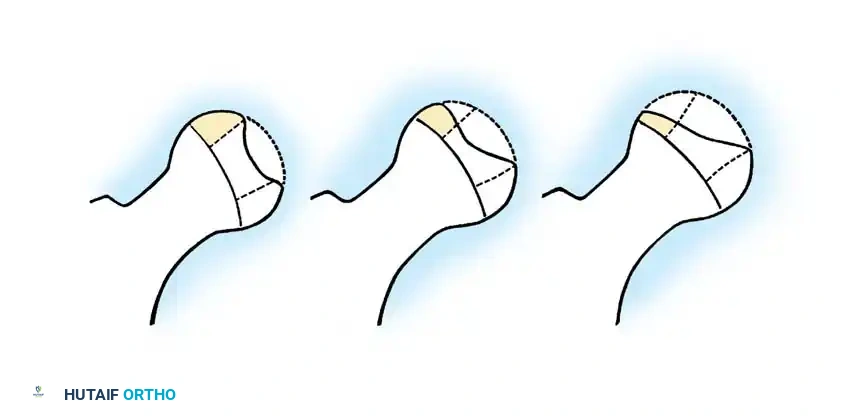

2. Salter-Thompson Classification

Salter and Thompson simplified early classification by measuring the extent of the subchondral fracture (crescent sign) in the superolateral femoral head on frog-leg lateral radiographs.

* Type A: Fracture line involves less than 50% of the superior dome (Good prognosis).

* Type B: Fracture line involves more than 50% of the superior dome (Fair/Poor prognosis, often requiring innominate osteotomy).

While Mukherjee and Fabry validated its accuracy, our institutional experience notes that subchondral fractures are visible early in only one-third of patients, limiting its universal application.

3. Herring Lateral Pillar Classification

The Herring classification is currently the most widely utilized and prognostically accurate system. It evaluates the height of the lateral pillar of the capital femoral epiphysis on an AP radiograph during the early fragmentation phase.

* Group A: No involvement of the lateral pillar (100% height maintained). Uniformly good outcomes.

* Group B: Greater than 50% of lateral pillar height maintained. Good outcomes if onset is < 9 years of age; less favorable if > 9 years.

* Group C: Less than 50% of lateral pillar height maintained. Worst outcomes, typically resulting in aspherical femoral heads regardless of age.